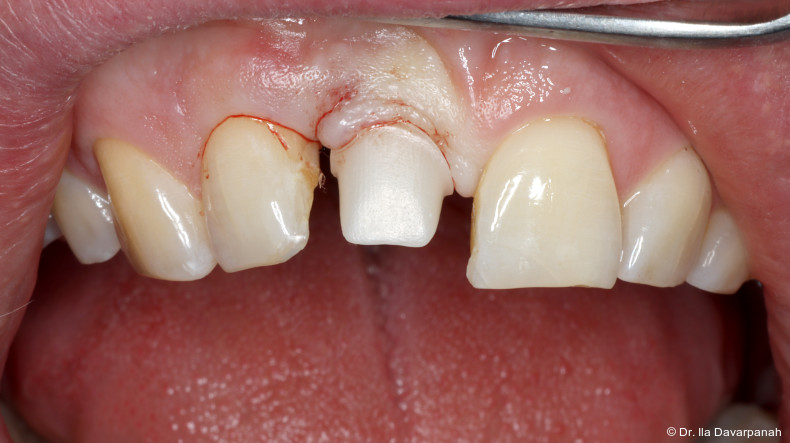

Neben patientenbezogenen und chirurgischen Faktoren spielt dabei auch das Implantatdesign eine wesentliche Rolle. Die vorliegende Falldokumentation zeigt eine Sofortimplantation Regio 11 mit digitaler Planung anhand von DICOM- und STL-Daten. Die präoperative Planung erfolgte softwaregestützt, die Implantatposition wurde prothetisch orientiert festgelegt. Klinisch und radiologisch lagen günstige Ausgangsbedingungen für eine Sofortimplantation mit Sofortversorgung vor.

Zur Erreichung einer hohen Primärstabilität wurde ein Implantat mit aggressivem Gewinde bei einem Außendurchmesser von 3,5 mm und einem Kerndurchmesser von ca. 2,8 mm eingesetzt. Ergänzend erfolgte eine unterpräparierte Bohrung. Solche Kombinationen aus Gewindedesign, Implantatgeometrie und Bohrprotokoll sind in der klinischen Praxis etabliert, erfordern jedoch eine sorgfältige Risikoabschätzung hinsichtlich der mechanischen Belastung des Implantatkörpers.

Postoperativ kam es trotz korrekter Implantatpositionierung und regelrechter Sofortversorgung zu einer Fraktur des Implantatkörpers im Bereich der Implantatschulter. Die radiologische Diagnostik mittels Röntgen und DVT zeigte ein Aufplatzen des Implantats im Übergangsbereich zwischen Konusverbindung und Implantatplattform. Das Frakturmuster deutete auf eine strukturelle Überlastung im hoch beanspruchten Schulterbereich hin. Implantatfrakturen stellen insgesamt eine seltene, jedoch für Patient und Behandler belastende Komplikation dar. Sie treten bevorzugt in Regionen mit erhöhten Biege- und Querkräften auf, insbesondere in der Frontzahnregion und bei frühzeitiger funktioneller Belastung.